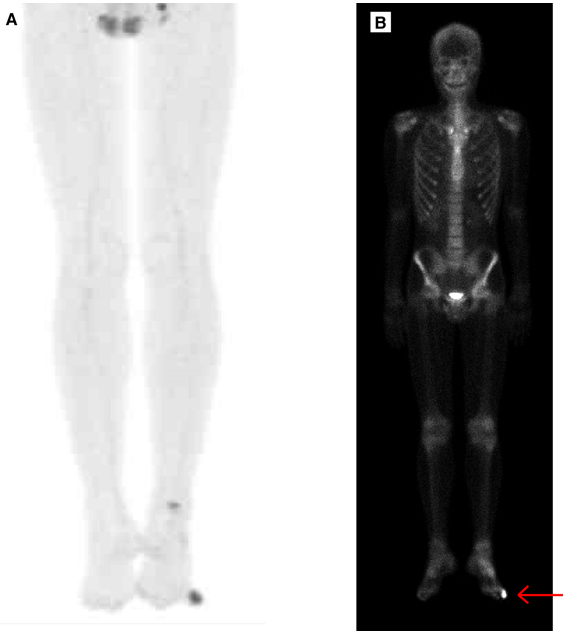

A 20-year-old Japanese male presented at our hospital due to pain and swelling of his left little toe for over one year. The patient had a history of trauma in the same toe two years previously. Examination revealed a swollen little toe on his left foot with skin ulceration. The nail showed degenerative changes (Figure 1). Family history and past medical history were unremarkable. Laboratory data, including serum total alkaline phosphatase and C-reactive protein, were within the upper limits of normal. Initial radiographic examination of the feet showed mixed calcification/ossification and osteolytic lesions with poorly defined margins and no apparent periosteal reaction in the distal and middle phalanges of the left little toe (Figure 2). X-ray examination also demonstrated fusion of the distal and middle phalanges of the right little toe, indicating that the fusion could be a normal variant ( (Figure 2), inset). On CT scan, popcorn-like calcification/ossification was clearly visualized with heterogeneous radiographic density (data not shown). Magnetic resonance imaging (MRI) scan showed tumors involving both the distal and middle phalanges with extraosseous masses, as well as disappearance of the subcutaneous fat (Figure 3). The tumor had a low-intermediate signal on T1-weighted image (T1WI), and a mixed low-to-high signal on SPAIR fat suppression. It demonstrated markedly heterogeneous Gd-contrast enhancement in both intraosseous and extraosseous portions. Both positron emission tomography (PET) scan with 18F-FDG and bone scintigraphy with 99mTc -MDP depicted uptake (SUVmax 4.0 in PET) in the little toe corresponding to the primary site (Figure 4). Open biopsy showed pleomorphic sarcoma without apparent osteoid. Immunohistochemically, tumor cells were positive for SMARCB1/INI1 (nuclear), but negative for CAM5.2, AE1/AE3, desmin, alpha-SMA, beta-catenin, CD68, S-100 protein, and FGF23, which suggested pleomorphic sarcoma (data not shown). Although osteoid was not evident in the biopsy specimen, clinical, radiological, and pathological features led to a diagnosis of OS of the middle and distal phalanges of the left little toe without distant metastasis. Since the tumors did not invade the proximal phalanx of the toe, disarticulation was performed at the metatarsophalangeal joint of the little toe. The amputated specimen was examined pathologically. As was the case with open biopsy, microscopy showed a proliferation of oval to polygonal tumor cells, with vesicular pleomorphic nuclei arranged in haphazard pattern, accompanied by irregular osteoid formation, staghorn vessels, and multinucleated tumor giant cells, which led to a pathological diagnosis of typical osteoblastic OS (Figure 5). The patient's clinical course after the disarticulation of the little toe was uneventful. The patient received adjuvant chemotherapy with high-dose methotrexate, doxorubicin, and cisplatin. No recurrence has been observed on 12-month follow-up. | ||||||